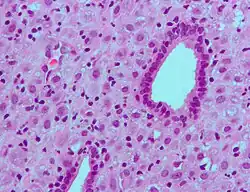

Micrograph showing changes to the endometrium due to progesterone (decidualization) H&E stain

Progesterone has key effects via non-genomic signalling on human sperm as they migrate through the female reproductive tract before fertilization occurs, though the receptor(s) as yet remain unidentified.[48] Detailed characterisation of the events occurring in sperm in response to progesterone has elucidated certain events including intracellular calcium transients and maintained changes,[49] slow calcium oscillations,[50] now thought to possibly regulate motility.[51] It is produced by the ovaries.[52] Progesterone has also been shown to demonstrate effects on octopus spermatozoa.[53]